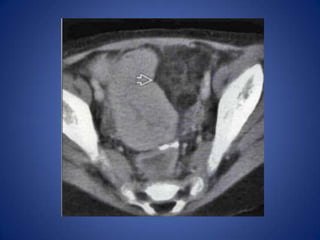

Urolithiasis

• Distal left ureteral stone may cause left lower

quadrant pain

• Diagnosis usually evident on CT

– Ureteral calculus, hydronephrosis, perinephric

stranding

Urolithiasis • Distal leftureteral stone may cause left lower quadrant pain • Diagnosis usually evident on CT – Ureteral calculus, hydronephrosis, perinephric stranding